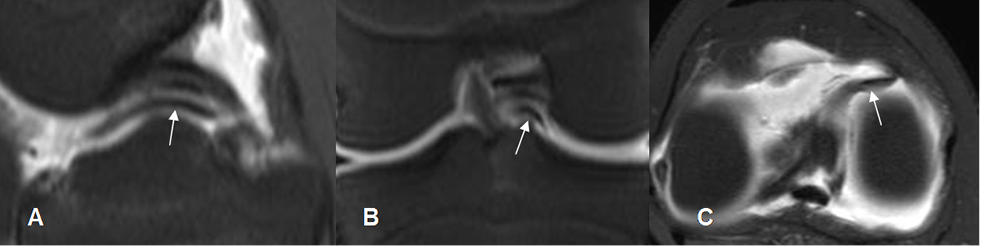

Fig 76. Ruptura meniscal radial.

A: RM sagital en T1, B: RM sagital en STIR y C: RM sagital en T2. Defecto en la parte medial del cuerno anterior del menisco, por ruptura radial.